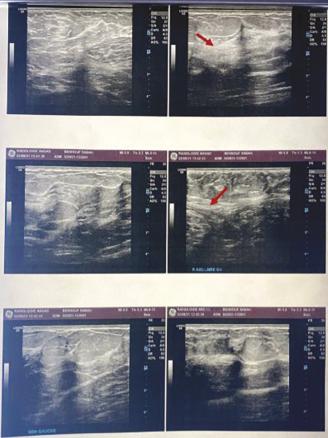

L’examen clinique révèle deux masses axillaires bilatérales, molles, bien limitées, de consistance glandulaire, indolores à la palpation, adhérentes au plan superficiel et mobiles par rapport au plan profond (fig. 1 ). Elles mesurent 5 cm sur 3 à droite et 4 cm sur 3 à gauche. La peau en regard est hyperpigmentée, sans individualisation de plaque aréolaire ou de mamelon. La mammographie (fig. 2 ) objective la présence de deux prolongements axillaires de tissu fibroglandulaire. Le complément échographique (fig. 3) révèle les mêmes résultats, concluant à des seins surnuméraires axillaires bilatéraux ACR2. Aucune lésion bénigne ou maligne n’est visualisée.

L’imagerie est primordiale pour la démarche diagnostique et le suivi. La mammographie révèle un aspect typique de parenchyme glandulaire mammaire de siège axillaire. À l’échographie, le diagnostic est évident lorsqu’une composante fibroglandulaire existe.6